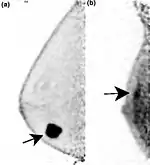

Two PEM images, including sites of tracer uptake

Purposeimaging modality used to detect breast cancer